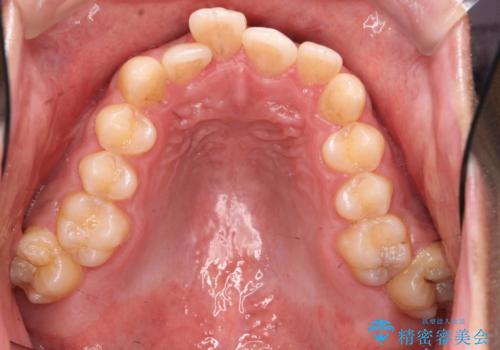

上顎両側7番(一番奥の歯)はすれ違っており、虫歯になっていました。

虫歯治療については